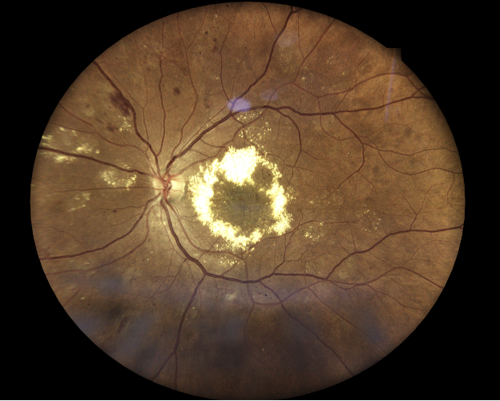

Fundus examination revealed pink, well-defined optic nerves bilaterally without evidence of neovascularization of the disc. There was extensive lipid exudation with associated macular edema in both eyes, along with numerous dot-and-blot and flame-shaped hemorrhages involving the posterior pole and extending into the equator bilaterally. The retinal arterioles appeared attenuated with arteriovenous crossing changes and an increased arteriolar light reflex, and findings were consistent with hypertensive and arteriosclerotic changes.

Additionally, diffuse exudation was noted throughout the equator, with a coinciding orangish-pink retinal hemorrhage observed superiorly in the right eye. Areas of anomalous retinal vasculature were identified in the inferotemporal and superonasal quadrants of the right eye. Overall, the clinical presentation was suggestive of a multifactorial retinopathy, most consistent with diabetic retinopathy with contributory sickle cell retinopathy.